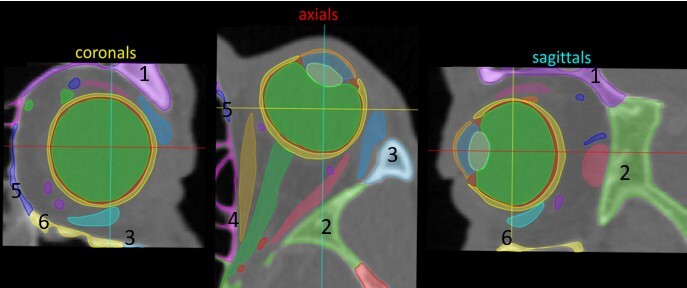

12

Label 1-7

A

1=Rt Maxilla (orbital plate)

2=Rt Lacrimal

3=Rt Ethmoid (lamina papyracea)

4= Rt Palatine (orbital plate)

5=Rt Frontal

6=Rt Sphenoid (greater wing)

7=Rt Zygoma

How well did you know this?

13

Label 8-11

8-Rt Superior orbital fissure

9-Rt Optic canal

10= Rt Nasal bone

11=Rt frontal process (maxilla)

14

Label 1-6

1=Lt Frontal bone

2=Lt Sphenoid bone (greater wing)

3=Lt Zygomatic bone

4=Lt Ethmoid bone (lamina papyracea)

5=Lt Lacrimal bone

6=Lt Maxilla (orbital plate)